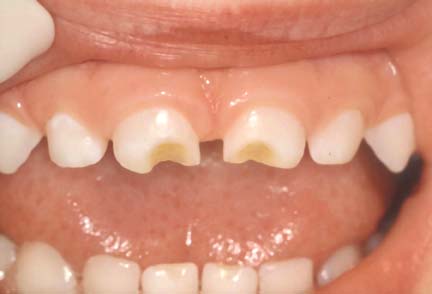

Also known as Early Childhood Caries or Nursing Caries, Baby Bottle Tooth Decay is caused by over exposure to sugary liquids. It is usually caused by putting a baby to bed with a bottle containing milk, juice, or soda, nursing babies on demand through the night, or allowing toddlers to graze with a sippy cup. This condition often destroys primary teeth, creating a need for major dental treatment. In addition, it will eventually damage your child’s permanent teeth if left untreated.

You can prevent this by following a few simple guidelines:

1) Never allow your child to fall asleep with a bottle containing milk, formula, breast milk, fruit juices, or any sweetened liquids.

2) Never give your baby a pacifier dipped in sugar or honey.

3) Only allow water in bottles and sippy cups used for grazing.

4) Wipe your baby’s gums with a clean gauze pad after each feeding, and begin brushing as soon as the first tooth appears.

5) Encourage children to drink from a regular cup by their first birthday.